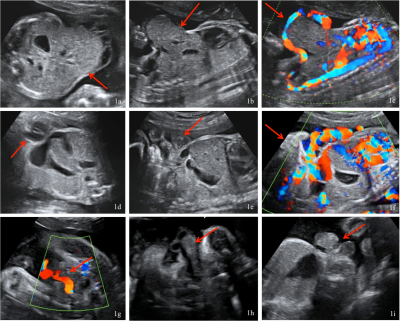

Základní metodou screeningu i diagnostiky vrozených rozštěpových vad břišní stěny je standardní dvoj-rozměrné ultrazvukové vyšetření (obrázek č. 1). Zobrazení 3D/4D ultrazvukem a magnetickou rezonancí může být v některých případech přínosné ke zpřesnění informace o místě defektu a vyhřezlých orgánech, význam těchto dvou novějších zobrazovacích metod však není zásadní.

Obrázek č. 1.: Standardní dvojrozměrné (2D) ultrazvukové vyšetření u plodu postiženého gastroschízou (1a), omfalokélou (1b) a extrofií močového měchýře (1c).

(Foto: MUDr. Veronika Frisová, Profema)